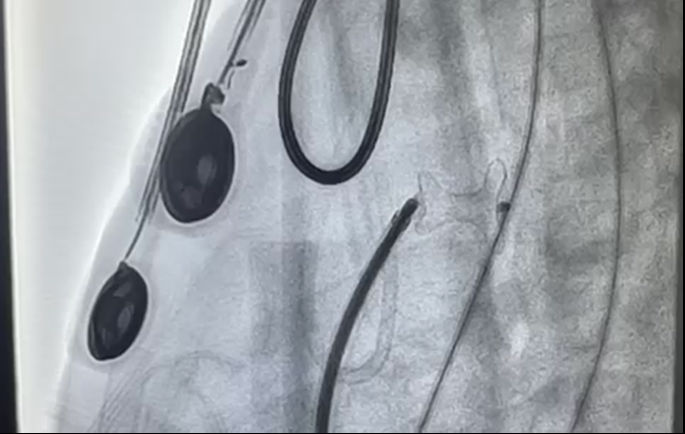

一小时后,亮亮的手术顺利完成,安全返回病房。紧接着,嘉嘉也被送进了手术室。手术十分顺利,仅历时半小时有余,嘉嘉便安全病房。术后两位患儿复查心脏彩超显示封堵器位置、形态正常,未见残余分流,均达到了预期效果。

嘉嘉术中封堵器顺利释放